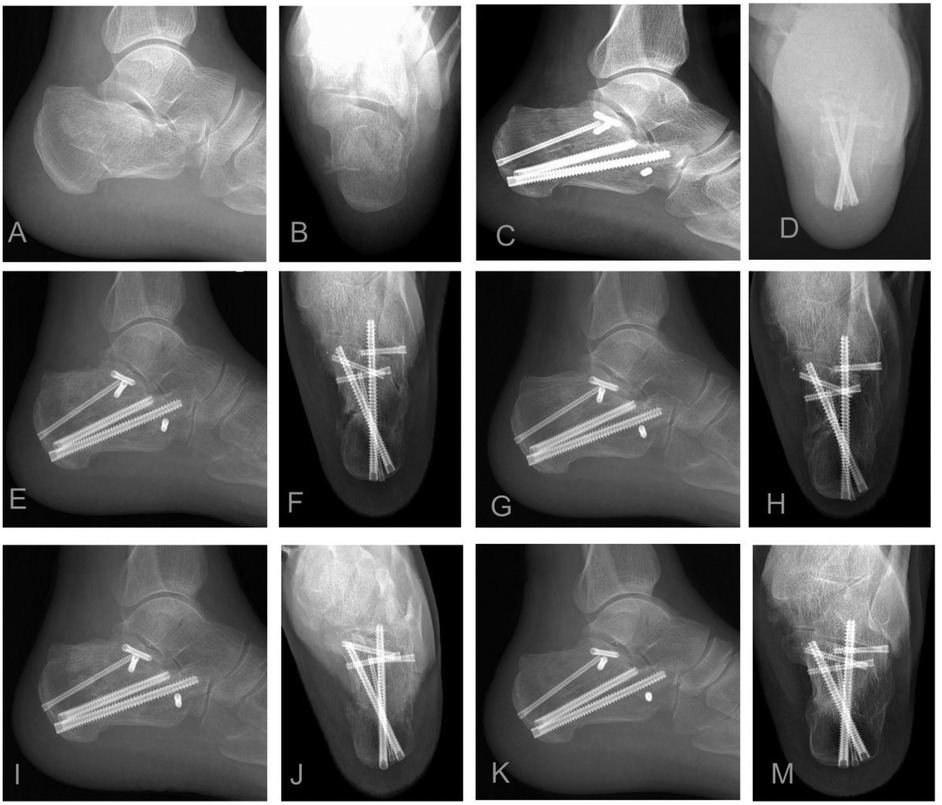

Figure 1

Twelve X-ray images labeled A to M display different views of a foot with surgical screws. Images C, E, G, I, K show lateral views with screws securing the bones. Images D, F, H, J, M show top-down views highlighting the screws' arrangement within the foot structure. Images A and B show the foot without surgical hardware.

Figure 1. Illustrative case: A 55-year-old male sustained a left sanders type IIB displaced intra-articular calcaneal fracture. (A,B) Preoperative lateral and axial radiographs: Reveal fracture comminution, loss of calcaneal height, increased width, and varus deformity. (C,D) Immediate postoperative radiographs: Demonstrate restoration of calcaneal height and width, anatomical reduction of the posterior facet, correction of varus deformity, and optimal implant positioning (sustentaculum tali screws and medial wall plating). (E–M) Serial postoperative radiographs (1, 3, 6, 12 months): Document maintained fracture reduction, stable implant position without evidence of loosening or migration, and progressive fracture union without collapse. Arthroscopic confirmation noted a posterior facet step-off <1 mm.